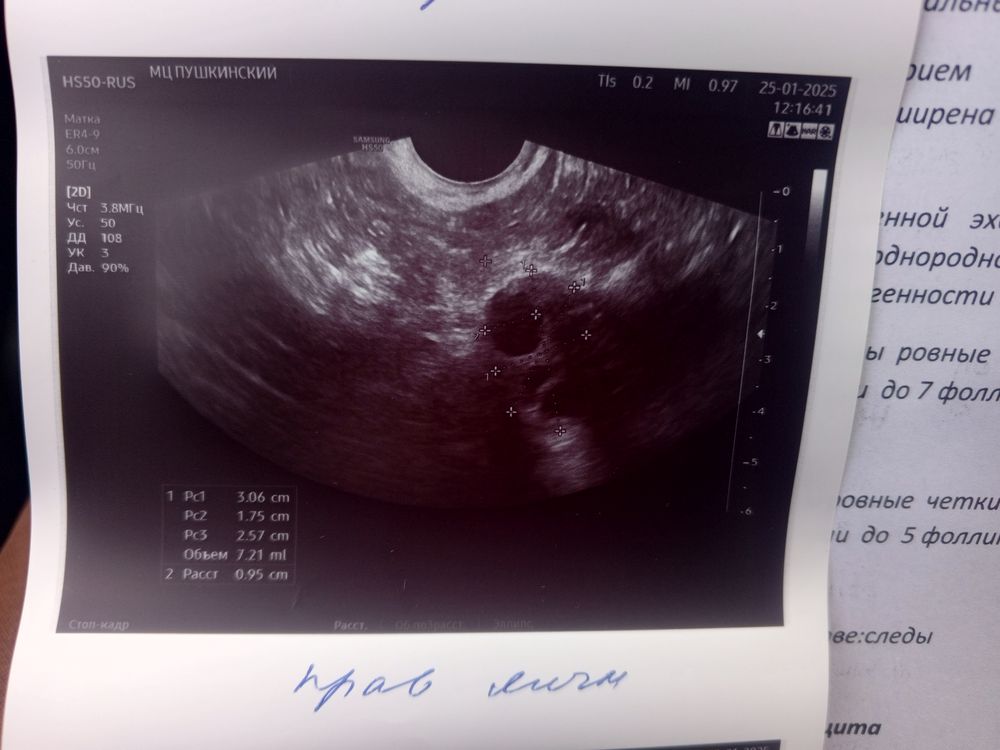

Аня, Изображение Изображение Изображение

Светлана , вот смотрите первая и вторая фаза, мне кажется у вас не было овуляции и эндометрий на 1 фазу, т.к. видно линию смыкания, но я не узист конечно, просто уже за кучу узи у себя различаю Изображение Изображение